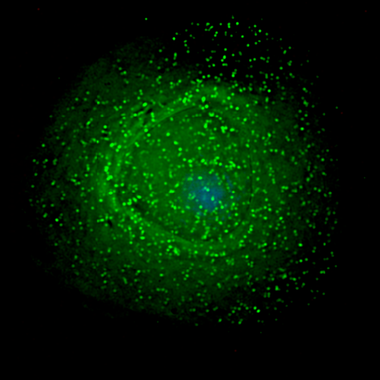

MacroH2A1.1 regula la respiración mitocondrial limitando el consumo de NAD+ en el núcleo de la célula